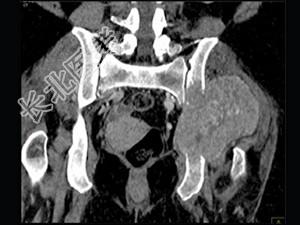

- 单项选择题男,56岁, 肺癌术后2年余,左髋部疼痛, 夜间加重,结合图像, 最可能的诊断是 ( )

B、骨转移